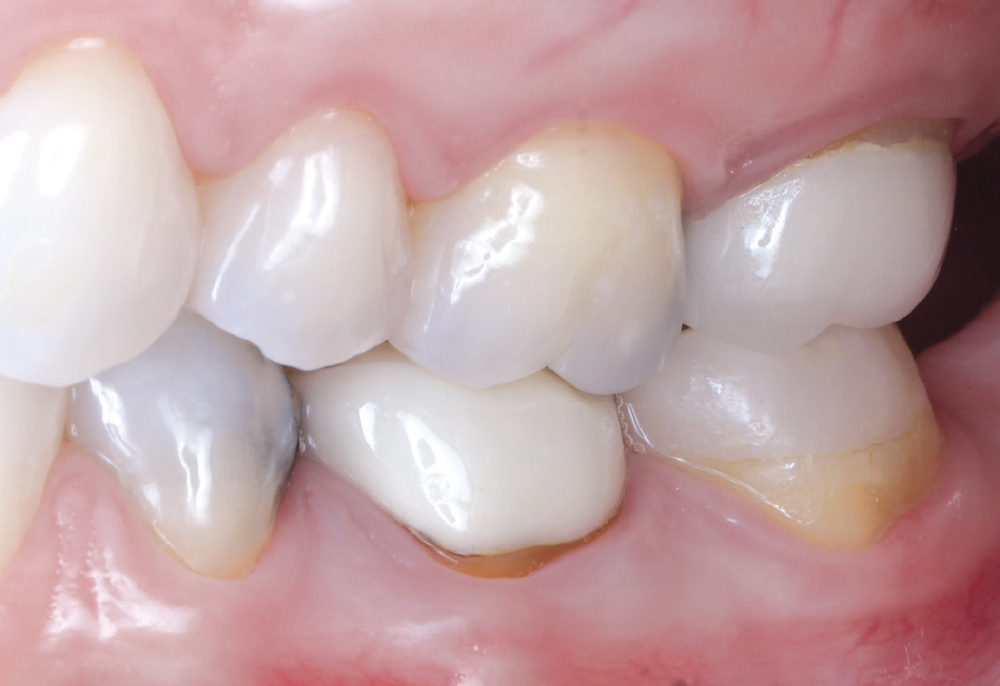

I enjoy using the glidewell.io system because I can provide a high-quality, same-day restoration. I’m in control of the contacts, shape, color and fit. The crown fits with minimal adjustments needed.

This was Nikole’s first experience with same-day dentistry, and she summed it up best: “I’m a fan! The new crown fit perfectly, with no return visit, no second round of anesthesia and barely any adjustments. The contacts are spot on, and flossing feels smooth.”